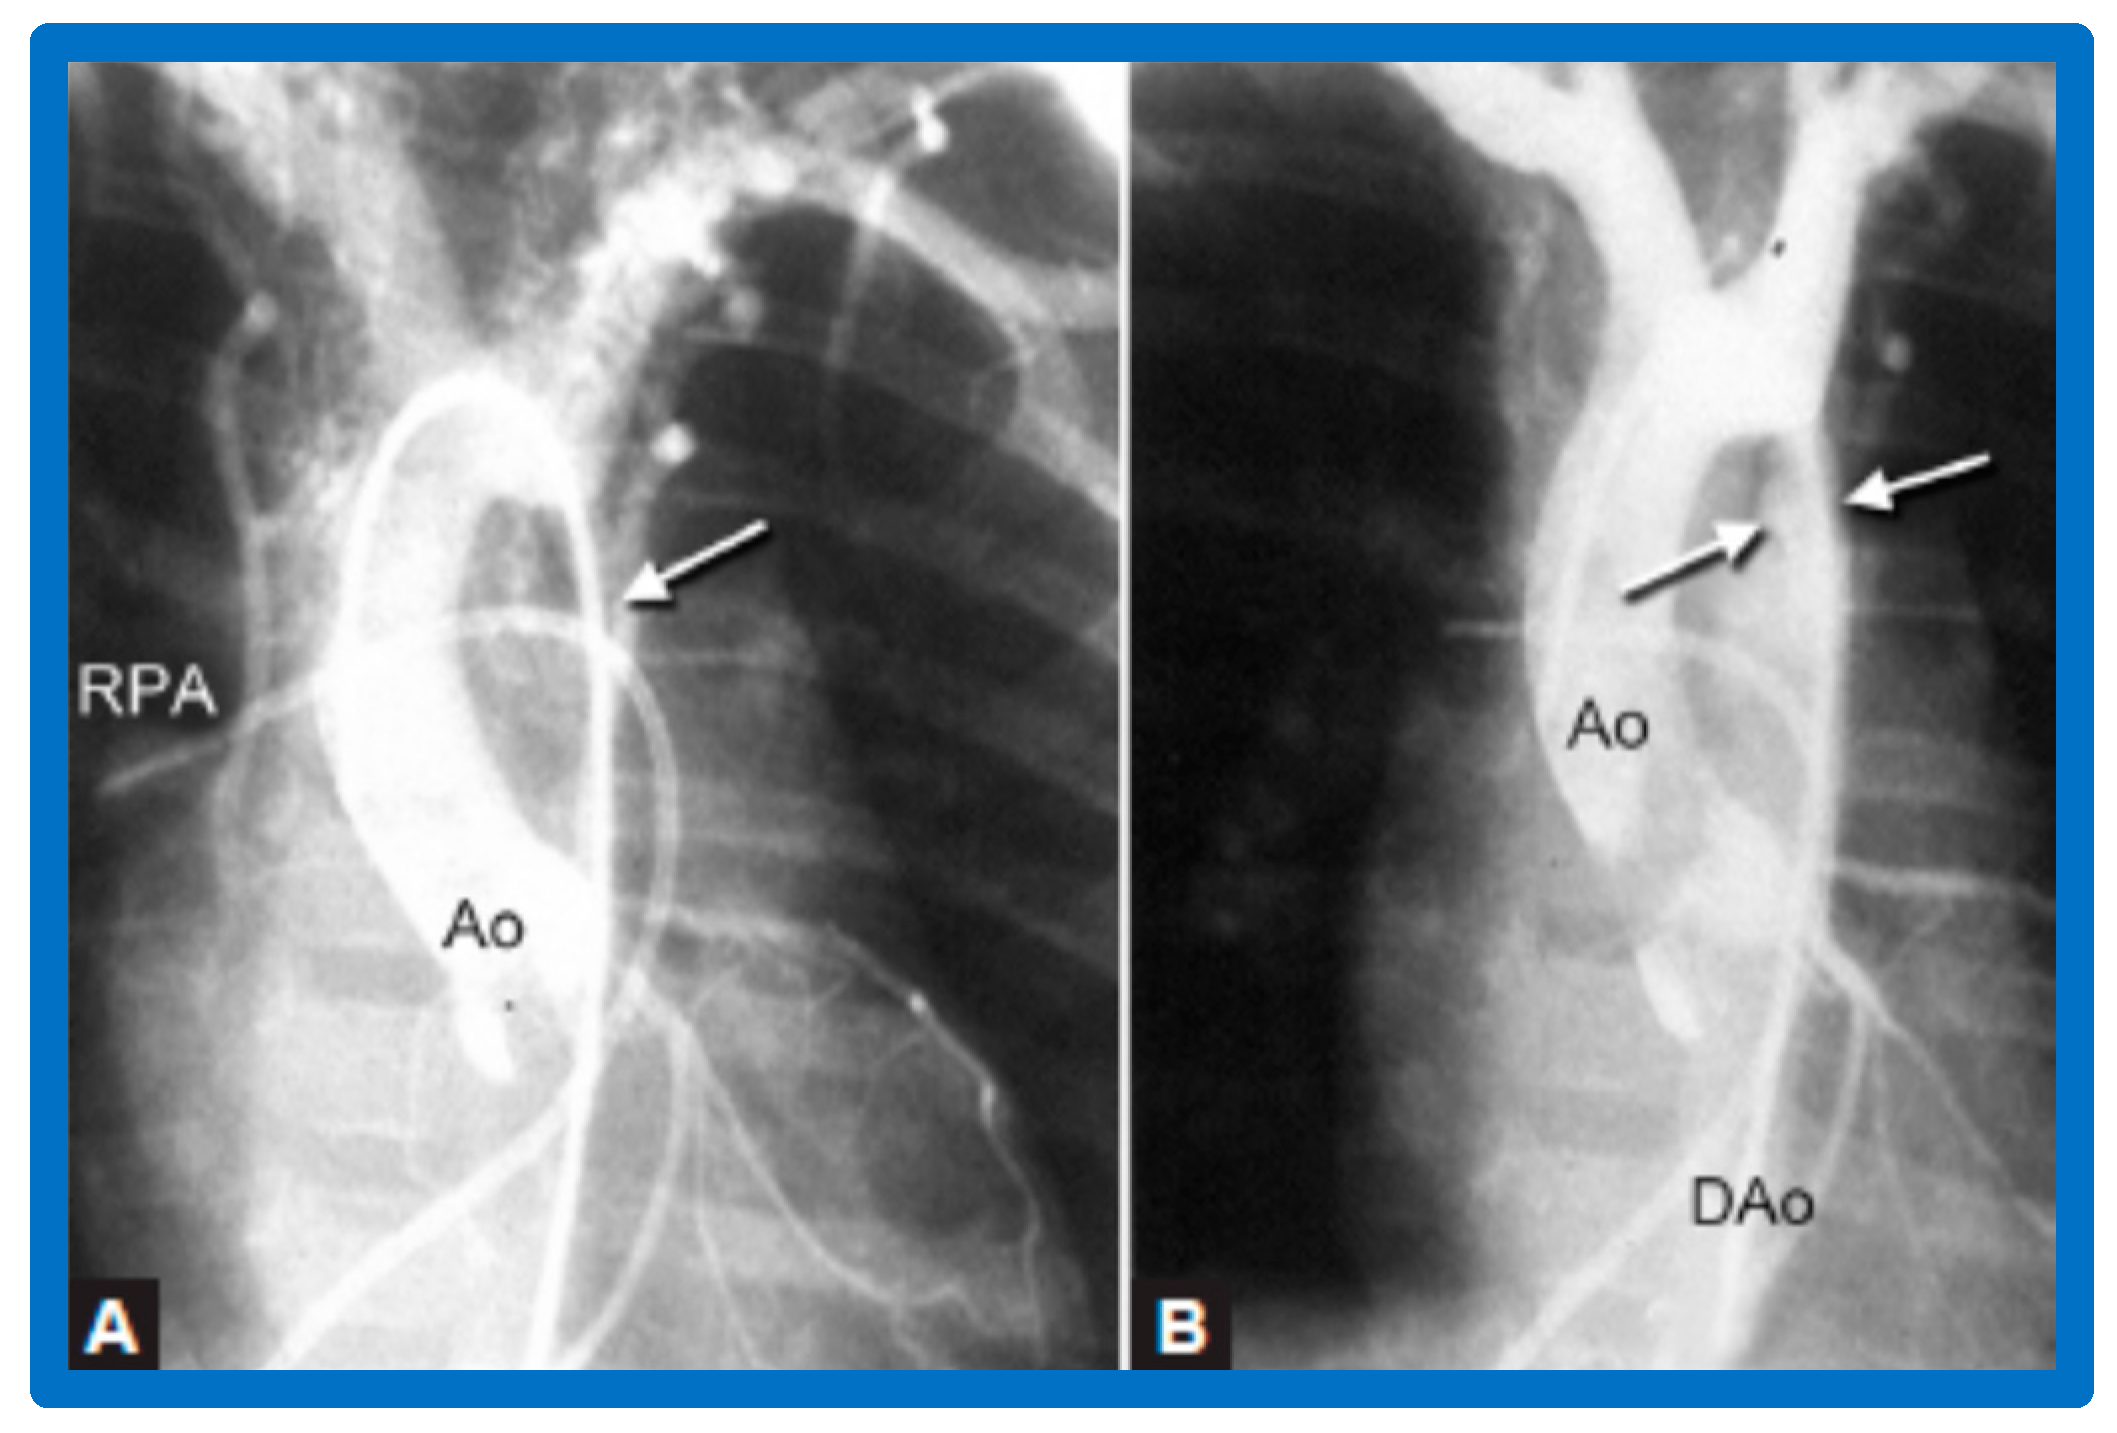

4.4. Aortic Coarctation, Postsurgical

5.4. Aortic Coarctation, Postsurgical